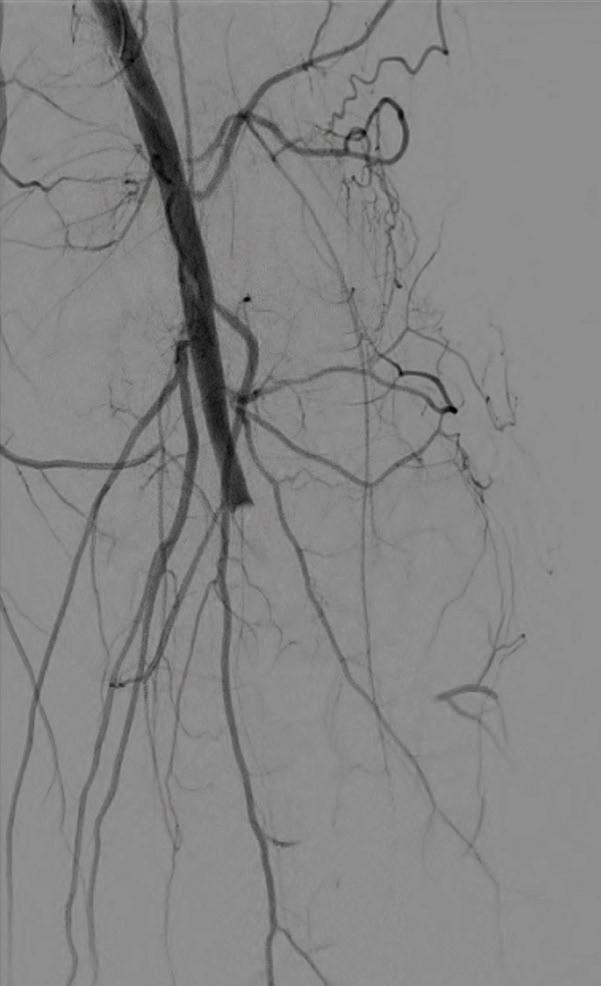

Post-intervention arteriogram

An excellent technical result was achieved. The SFA was widely patent with no significant residual stenosis. The posterior tibial and peroneal arteries were widely patent with brisk flow and no residual stenosis. Significantly improved flow was identified to the foot (Figure 4).